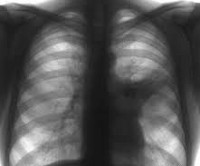

Диагностические предположения подтверждаются на основании данных рентгенографии легких: на снимках выявляются гомогенные интенсивные тени в форме треугольника, имеющие четко очерченные границы, снижение структурности корня. Иногда сегментарную пневмонию удается выявить только при динамическом исследовании, когда появляется ателектатический компонент, придающий границам поражения характерную четкость. В периферической крови определяются острые воспалительные изменения, включающие лейкоцитоз, сдвиг формулы влево повышение СОЭ, наклонность к анемии.

Основной метод диагностики пневмонии – рентгенологическое исследование (на снимках области поражения выглядят как темные пятна разного размера и формы). Для определения возбудителя болезни и его чувствительности к терапии проводятся клинические анализы крови, мокроты.